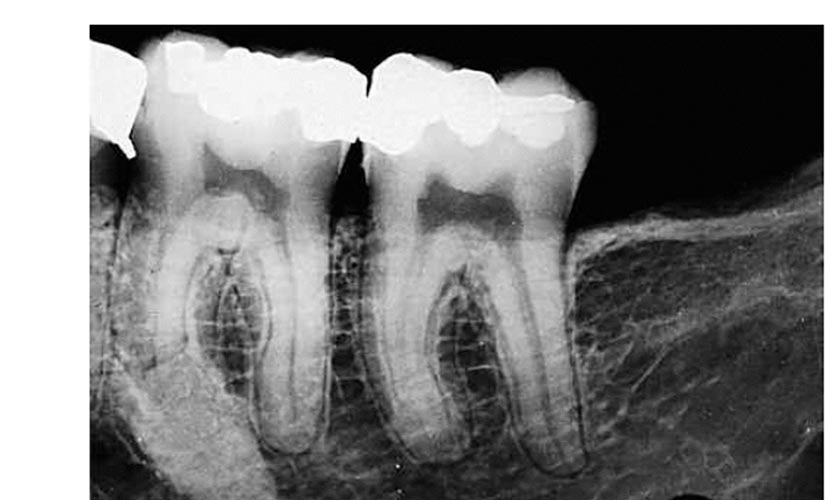

Зонування ПДЛ, холодовий тест, порівняльна перкусія, пальпація, дрілл тест, вибіркова анестезія, трейсинг, порівняння інформативності КТ та інтраорального тесту, правильні укладання для проведення якісних рентгенографічних досліджень, як своїми руками зробити позиціонер для інтерпроксимального знімка. Складні клінічні кейси, які потребують клінічного досвіду.

А також діагностика одонтогенних та неодонтогенних патологій за знімком.